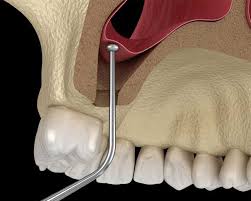

اگر برای ایمپلنت دندان در فک بالا به شما گفتهاند «استخوان کافی ندارید»، لیفت سینوس (Sinus Lift) یک راهحل علمی، ایمن و قابل پیشبینی است. امروزه با تکنیکهای جراحی لیفت سینوس باز و جراحی لیفت سینوس بسته میتوان حتی در موارد تحلیل شدید استخوان هم ایمپلنت موفق انجام داد — آن هم با درد کمتر، دقت بالاتر و نتایج ماندگار.

اگر در فک بالای دهان استخوان کافی برای ایمپلنت وجود نداشته باشد، لیفت سینوس یا sinus lift تنها یک «گزینه» نیست؛ بلکه یک پیشنیاز علمی برای درمان ایمن و ماندگار است. کاهش ارتفاع استخوان پس از کشیدن دندان یا با افزایش سن، باعث پایینآمدن سینوس ماگزیلاری میشود. جراحی سینوس لیفت تهران دقیقاً برای حل همین چالش طراحی شده است: ایجاد فضای امن برای استخوانسازی کنترلشده و آمادهسازی فک برای ایمپلنت پایدار.

لیفت سینوس دقیقاً چه کاری انجام میدهد؟

به زبان ساده، ما:

-

کف سینوس را بهآرامی بالا میبریم

-

فضای ایجادشده را با مواد استخوانساز پر میکنیم

-

و بدن را تشویق میکنیم استخوان جدید بسازد

این فرایند، پایهای محکم برای ایمپلنت ایجاد میکند؛ درست مثل تقویت فونداسیون قبل از ساخت ساختمان.

در جراحی سینوس لیفت بسته این کار با حداقل تهاجم انجام میشود.

در جراحی لیفت سینوس باز، وقتی تحلیل شدیدتر است، مسیر دسترسی مستقیمتر خواهد بود.